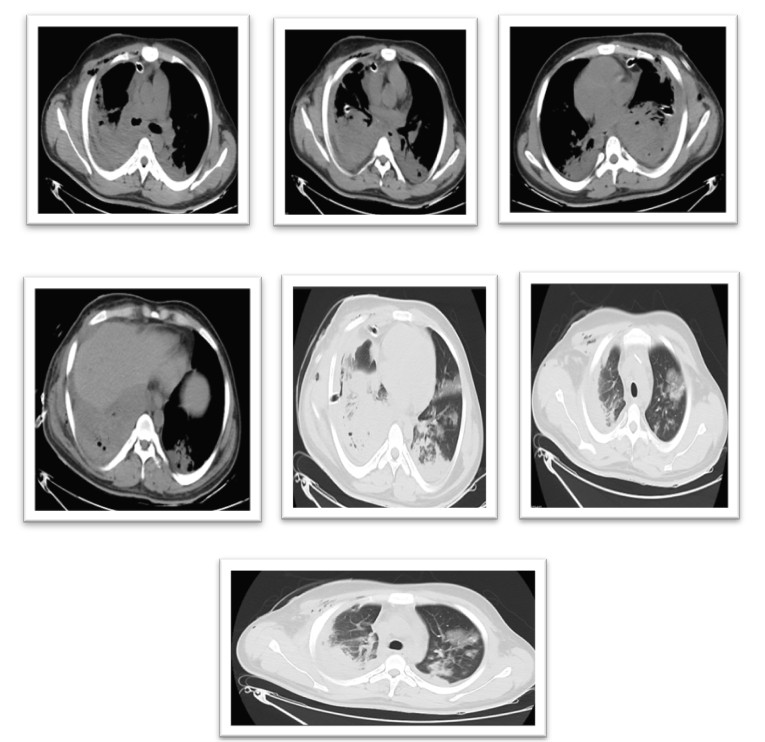

| CT Chest (19/9/25) | Large multiloculated pleural collection with enhancing wall, thick septations, diffuse pleural thickening, and right ICD in situ. |

From an oncological perspective, germ cell tumors (GCTs) of the testis have an excellent prognosis when managed appropriately with surgery and adjuvant chemotherapy. However, neglecting periodic follow-up and tumor marker monitoring increases the risk of recurrence and distant metastasis. Pleural metastasis typically occurs through hematogenous spread or lymphatic dissemination, leading to pleural thickening, effusion, or loculated empyema-like collections. In this case, imaging and pleural histopathology confirmed the metastatic nature of the lesion.